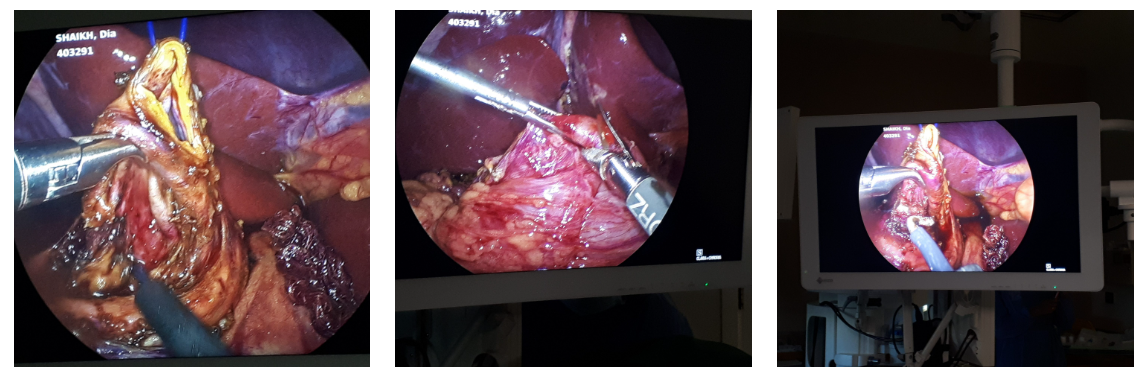

2 years old boy with trisomy 21 was referred to PICU with respiratory distress and multiple Lung consolidations. Child was stabilized and assessed thoroughly which revealed presence of extremely rare bilateral Morgagni’s hernia in the diaphragm. Almost half of thoracic cavity was filled with abdominal contents leading to collapse consolidation of bilateral lung tissues. 20×15 cm2 diaphragmatic defect through which most of colon, right lobe of liver, stomach , omentum and small bowel was found herniating into the chest. The contents were reduced into abdomen, the hernial sac was excised from chest and heart, the diaphragmatic defect was repaired and space was created for the lungs to expand and function properly